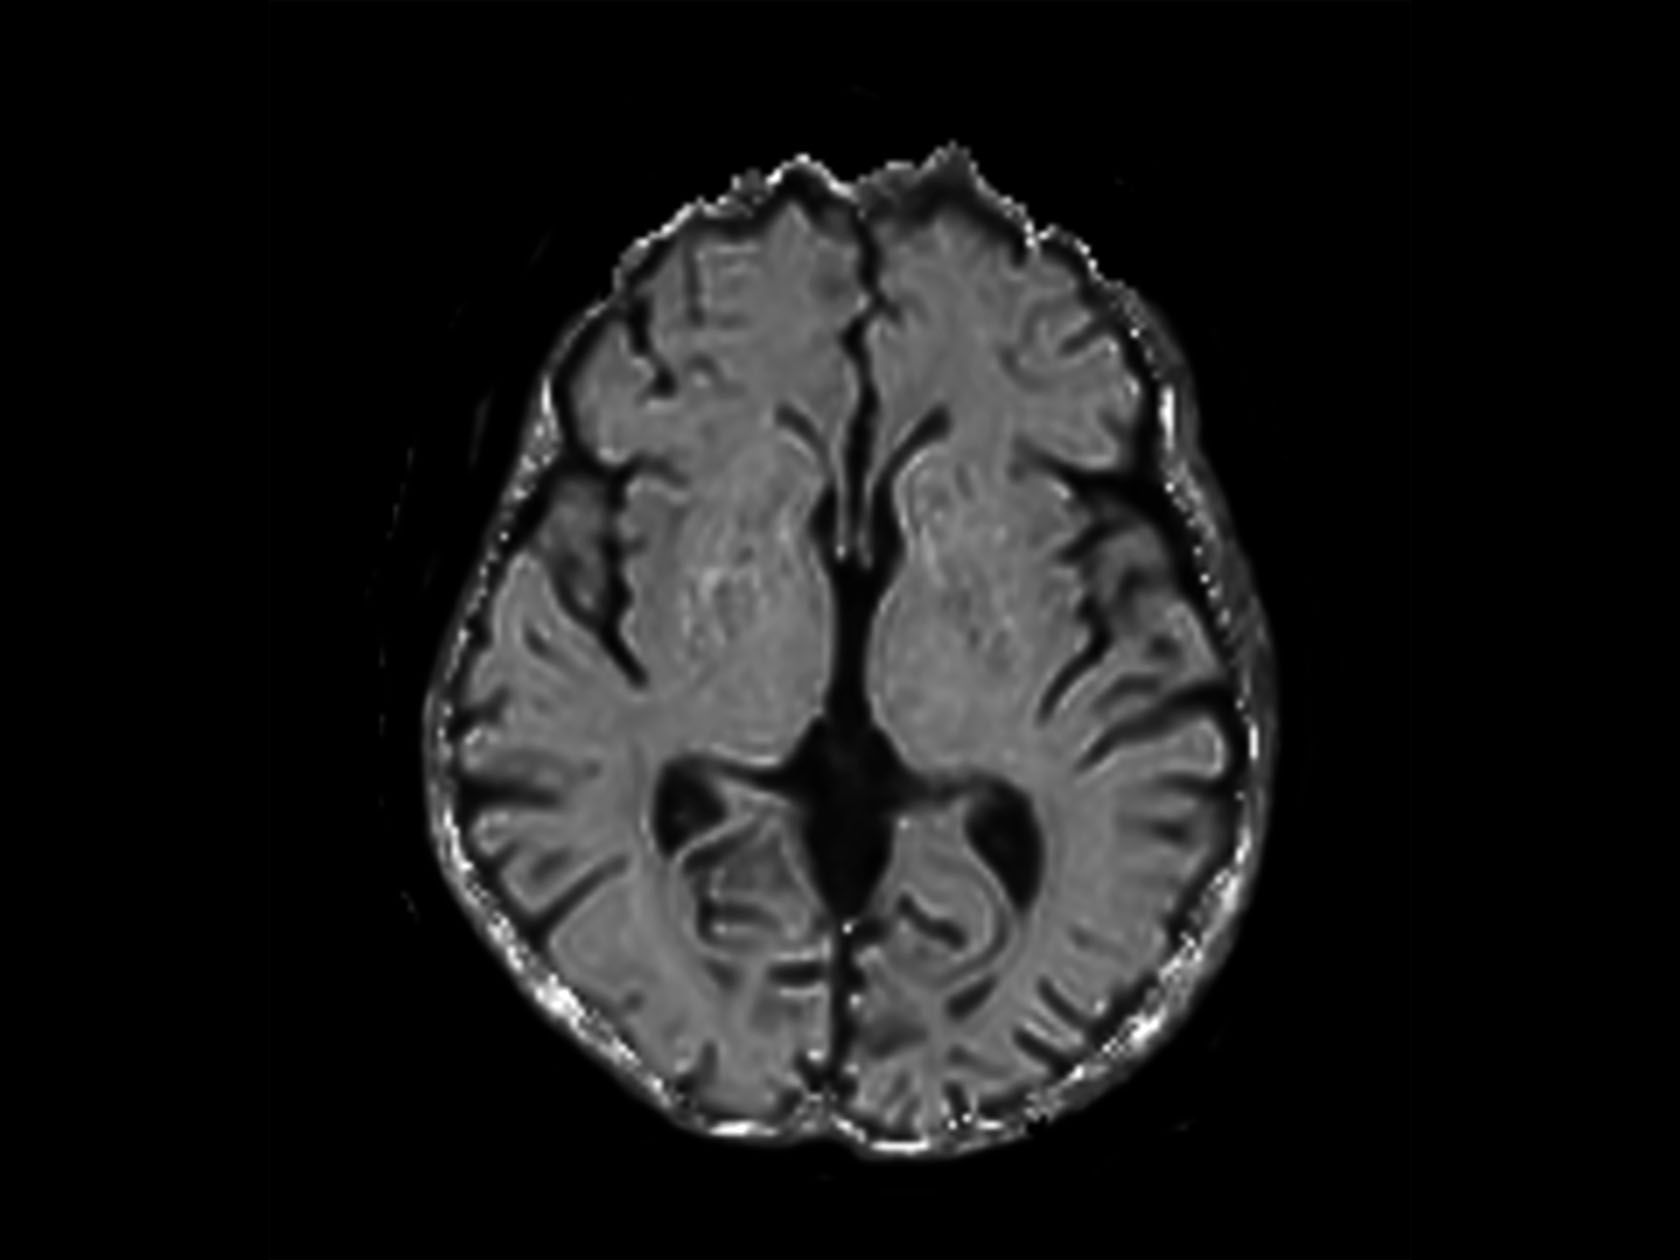

Axial T2w MultiVane XD with ComforTone

Coronal T2w FLAIR with ComforTone